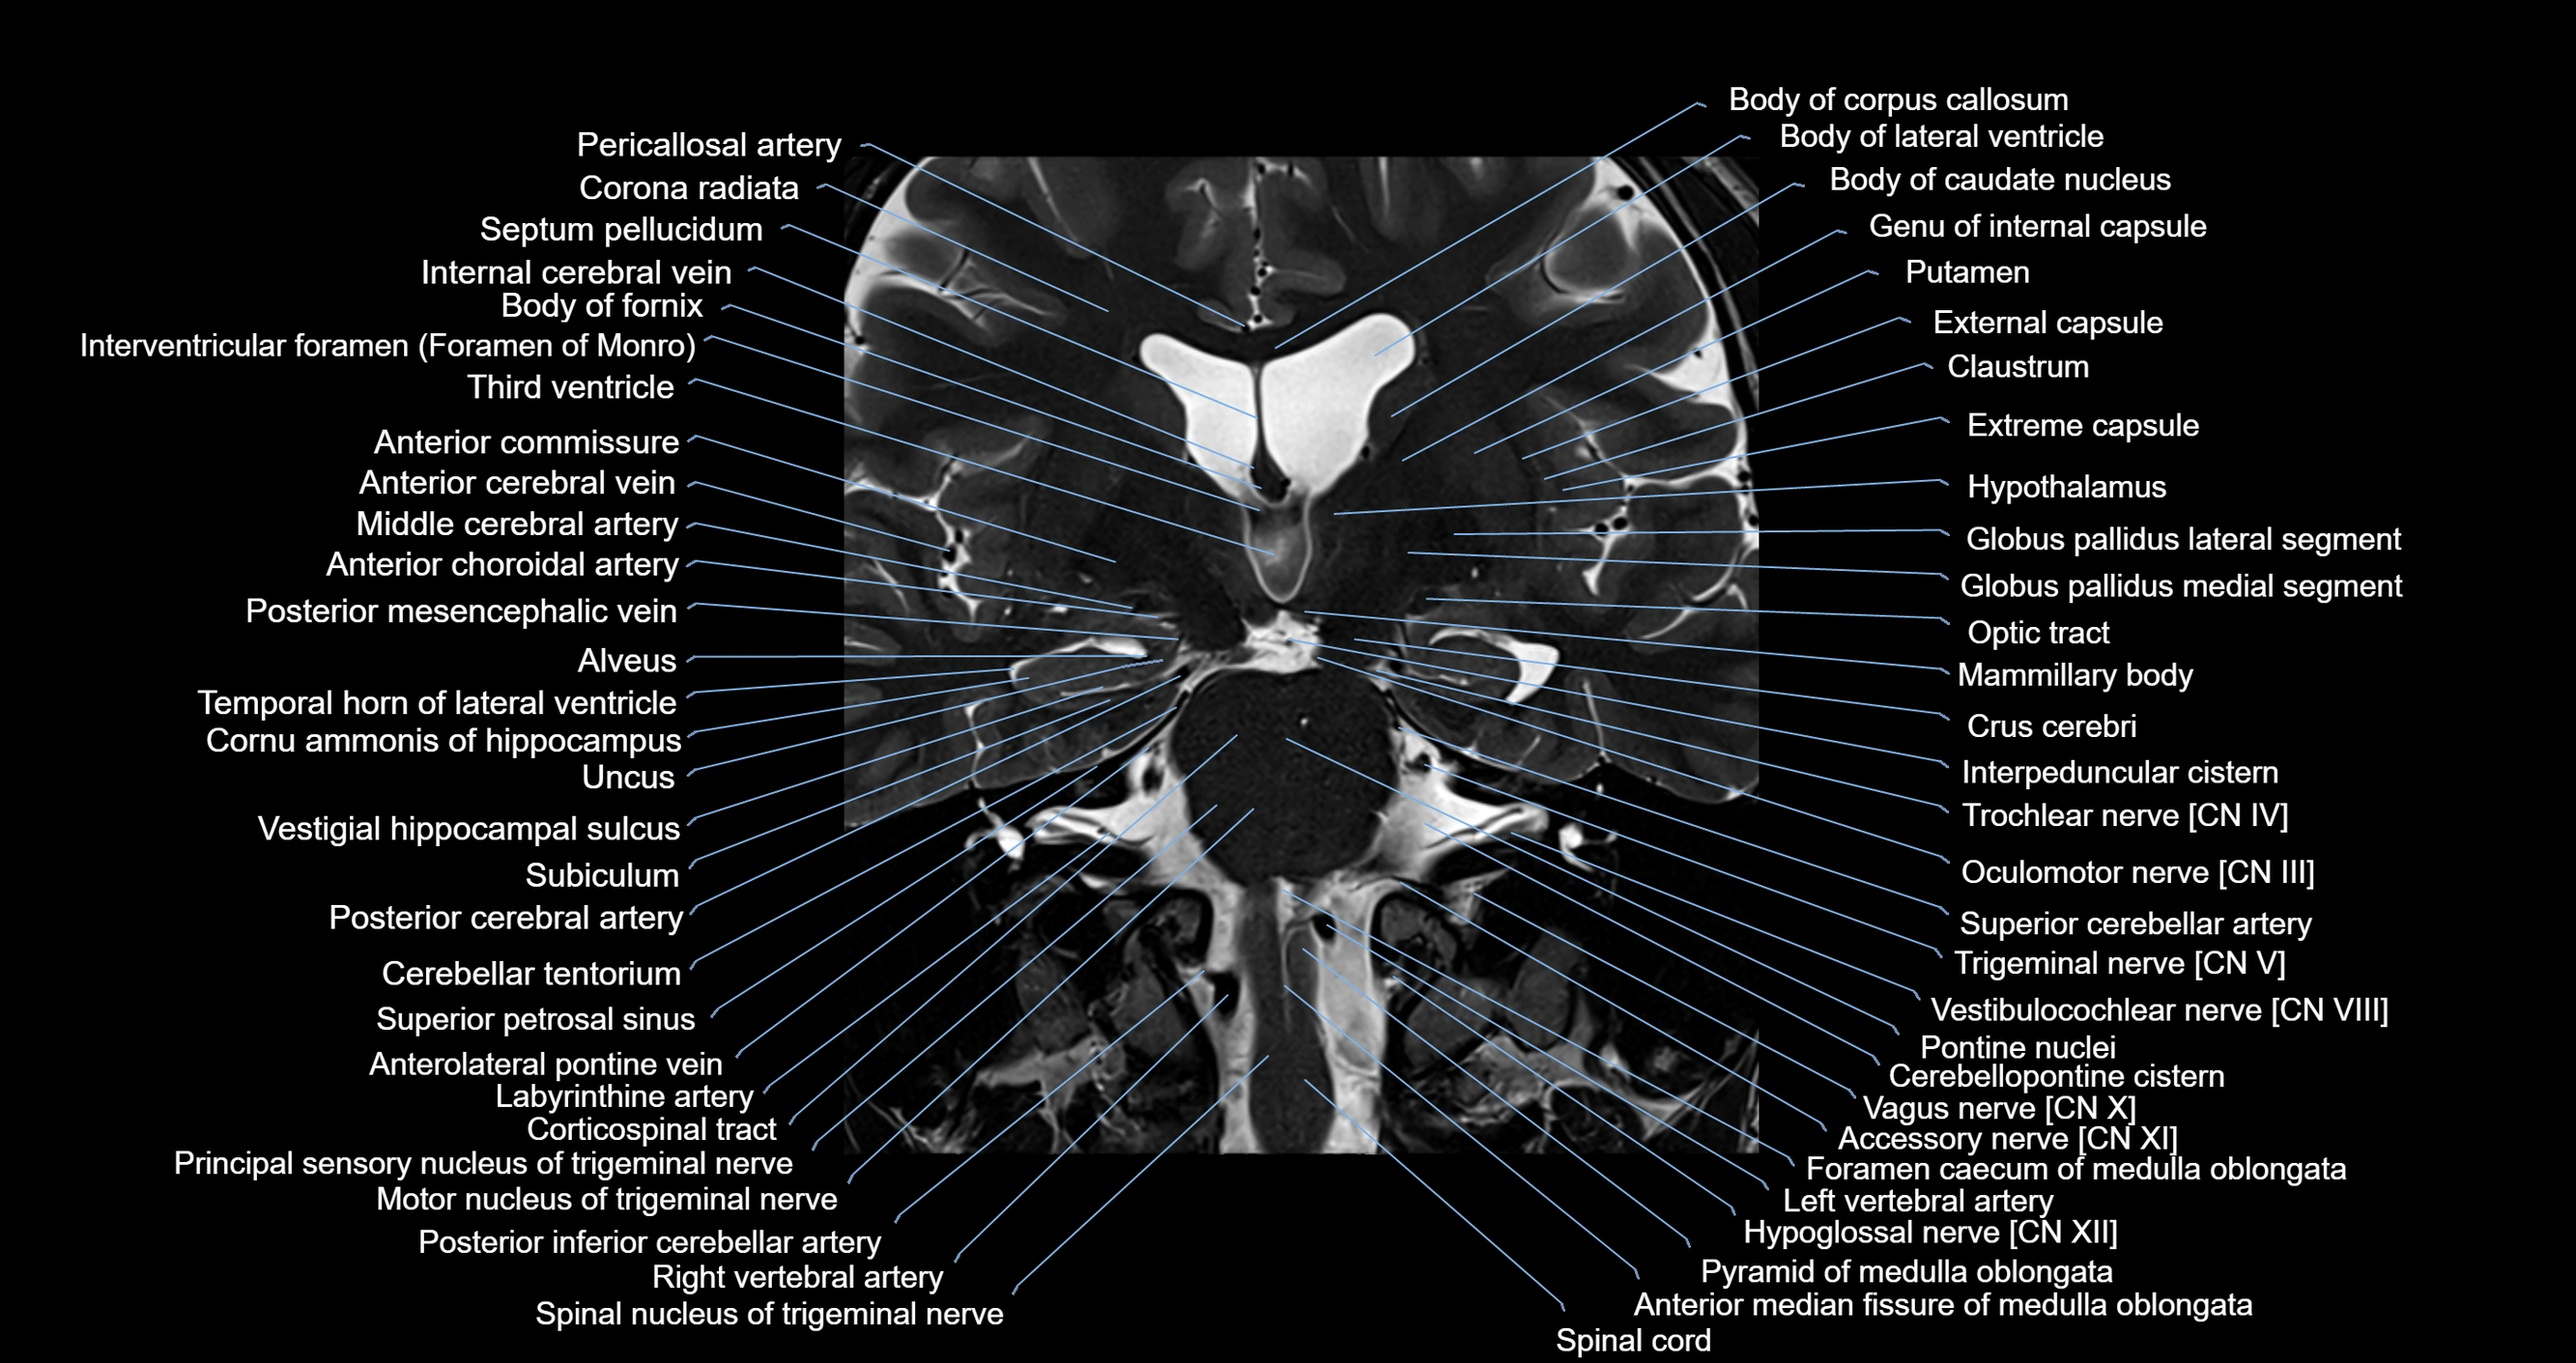

- Abducens nerve (Cranial nerve VI)

- Accessory Nerve (Cranial nerve XI)

- Anterior median fissure of medulla oblongata

- Anterolateral pontine vein

- Anteromedian medullary vein

- Body of caudate nucleus

- Body of corpus callosum

- Body of fornix

- Body of lateral ventricle

- Cerebellar tentorium

- Cerebellopontine cistern

- Cerebral crus

- Claustrum

- Column of fornix

- Corona radiata

- Corticospinal tract

- Crus cerebri

- External capsule

- Extreme capsule

- Fourth ventricle

- Globus pallidus external segment

- Globus pallidus internal segment

- Head of caudate nucleus

- Hypoglossal Nerve (Cranial nerve XII)

- Hypothalamus

- Inferior petrosal sinus

- Internal carotid artery

- Internal cerebral vein

- Interpeduncular Cistern

- Labyrinthine artery

- Left Vertebral Artery (Intracranial Part)

- Left vertebral artery

- Mammillary body

- Medial lemniscus

- Medial longitudinal fasciculus

- Middle cerebellar peduncle

- Motor nucleus of trigeminal nerve

- Nodule of vermis

- Oculomotor Nerve (Cranial Nerve III)

- Pontine nucleus

- Posterior cerebral artery

- Posterior inferior cerebellar artery

- Posterior limb of internal capsule

- Principal sensory nucleus of the trigeminal nerve

- Principal sensory nucleus of trigeminal nerve

- Putamen

- Pyramid of medulla oblongata

- Septum pellucidum

- Spinal cord

- Spinal lemniscus

- Spinal nucleus of trigeminal nerve

- Superior cerebellar artery

- Superior cerebellar peduncle

- Superior petrosal sinus

- Tegmentum of pons

- Temporal horn of lateral ventricle

- Third ventricle

- Trigeminal nerve (Cranial nerve V)

- Trochlear nerve (Cranial nerve IV)

- Uncus

- Vagus nerve (Cranial nerve X)

- Vestibulocochlear nerve (Cranial nerve VIII)